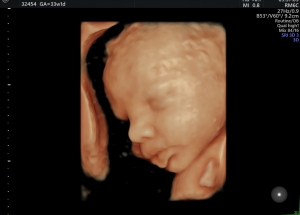

Sie können sich rund um die Uhr selbst den gewünschten Termin buchen. Besuchen Sie ggf. vorab den „Schwangerschaftskalender“ und dann die unsere Terminvergabe auf